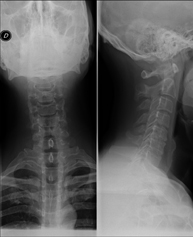

- RX Columna cervical

Técnica mediante la cual, utilizando rayos X, se obtienen imágenes de la columna cervical para su estudio. Indicaciones: traumatismo, contractura cervical, dolor articular.

Técnica mediante la cual, utilizando rayos X, se obtienen imágenes de la columna cervical para su estudio. Indicaciones: traumatismo, dolor cervical.